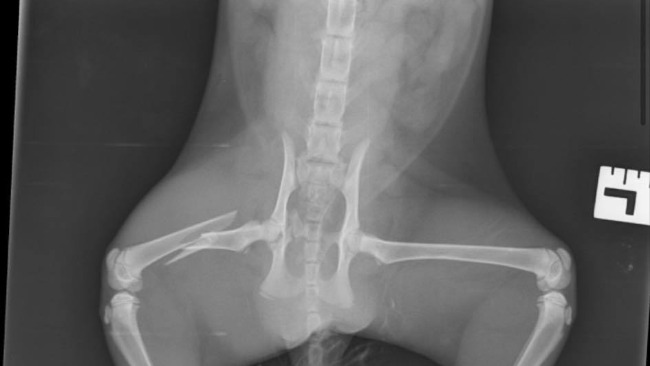

W trakcie pracy na trasie Leżajsk-Rzeszów znalazłam przy ulicy rannego młodego kota (około 1,5 miesięczna kotka), który jest prawdopodobnie bezdomny, ponieważ po poszukiwaniach właściciela okazało się że jest tylko dokarmiany. Kilkanaście razy dzwoniłam na straż miejską w Leżajsku, nikt nie odebrał. Niezwłocznie zawiozłam krwawiącą kotkę na wstępne badanie do lecznicy, gdzie dostała leki przeciwbólowe i przeciwkrwotoczne. Po dokładnym badaniu w klinice i zdjęciu rentgenowskim okazało się że ma złamaną kość udową i pękniętą miednice. Aktualnie kot przebywa w szpitalu Alfavet w Rzeszowie. Konieczna jest operacja złamanej nogi, jednak koszty są wysokie i całość opiewa na kwotę około 2000 zł. Po wykonaniu zabiegu kotka będzie potrzebowała opieki i kochającego domu, którego nie jestem w stanie zapewnić ponieważ posiadam już dwa psy i dwa koty…